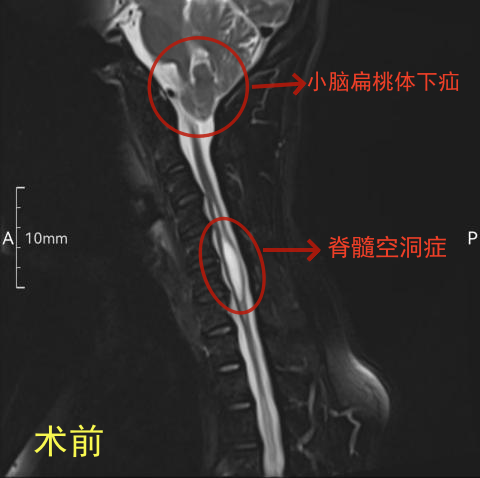

近日,43岁的王大姐听说贵医附院神经外科硕士、主治医师杨人,在都匀的贵医大三附院神经外科长期坐诊,特慕名前来就诊。王大姐告诉杨医生,她的颈肩部疼痛和双上肢麻木已经3年多了,日常生活和工作都受到了极大影响。经过详细检查,发现王大姐患上了小脑扁桃体下疝、脊髓空洞症。

术后复查,王大姐的小脑扁桃体下疝明显缓解,脊髓空洞明显缩小。

小脑扁桃体下疝的病理特点是:小脑扁桃体下部由颅腔内经枕骨大孔疝入椎管,由背侧压迫脊髓。约有56%的小脑扁桃体下疝患者会并发脊髓空洞症。会出现头痛、头面部麻木、上肢肌力减弱、肩臂部痛、温觉减退、吞咽困难、眩晕、恶心、共济失调,甚至瘫痪等一系列复杂的临床症状。